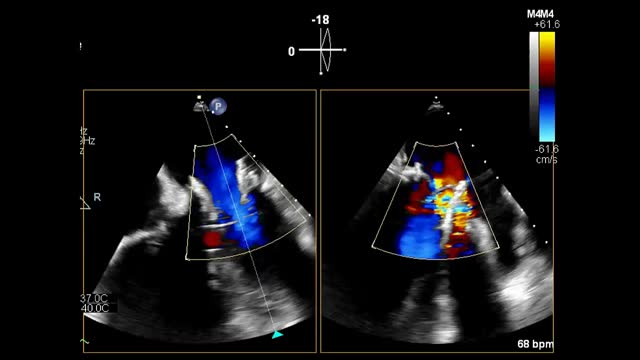

We describe the case of an 85-year-old man who underwent mitral replacement surgery with a biological prothesis (Carpentier-Edwards SAV 29) in 2011. In October 2020, he developed signs of heart failure. An echocardiogram was performed, revealing severe mitral bioprosthetic regurgitation, due to cusp prolapse (Video 1); preserved biventricular systolic function and major pulmonary hypertension. Due to his advanced age, frailty and having undergone previous cardiac surgery, the risk of new surgery was deemed too high. The decision was taken to perform a percutaneous mitral valve-in-valve implantation of a Sapiens 3 Ultra-29. The valve was inserted via transseptal puncture, with transesophageal echocardiogram and fluoroscopy guidance (Video 1). During valve deployment, rapid ventricular pacing was applied. After valve implantation, a small peri-prothesis leak was observed. There was no interference with the adjacent cardiac structures (Video 2); the mean transvalvular gradient was 5mmHg. The patient improved and was discharged five days later.

(A and B) Severe mitral prothesis regurgitation due to cusp prolapse, jets directed posterior-laterally and to the left atrial appendage; implantation of an Edwards Sapiens 3 Ultra-29 valve, with transesophageal echocardiography (C) and fluoroscopy (D) guidance; (E) final result: no signs of interference in the adjacent cardiac structures; a small lateral peri-prothesis leak was observed.